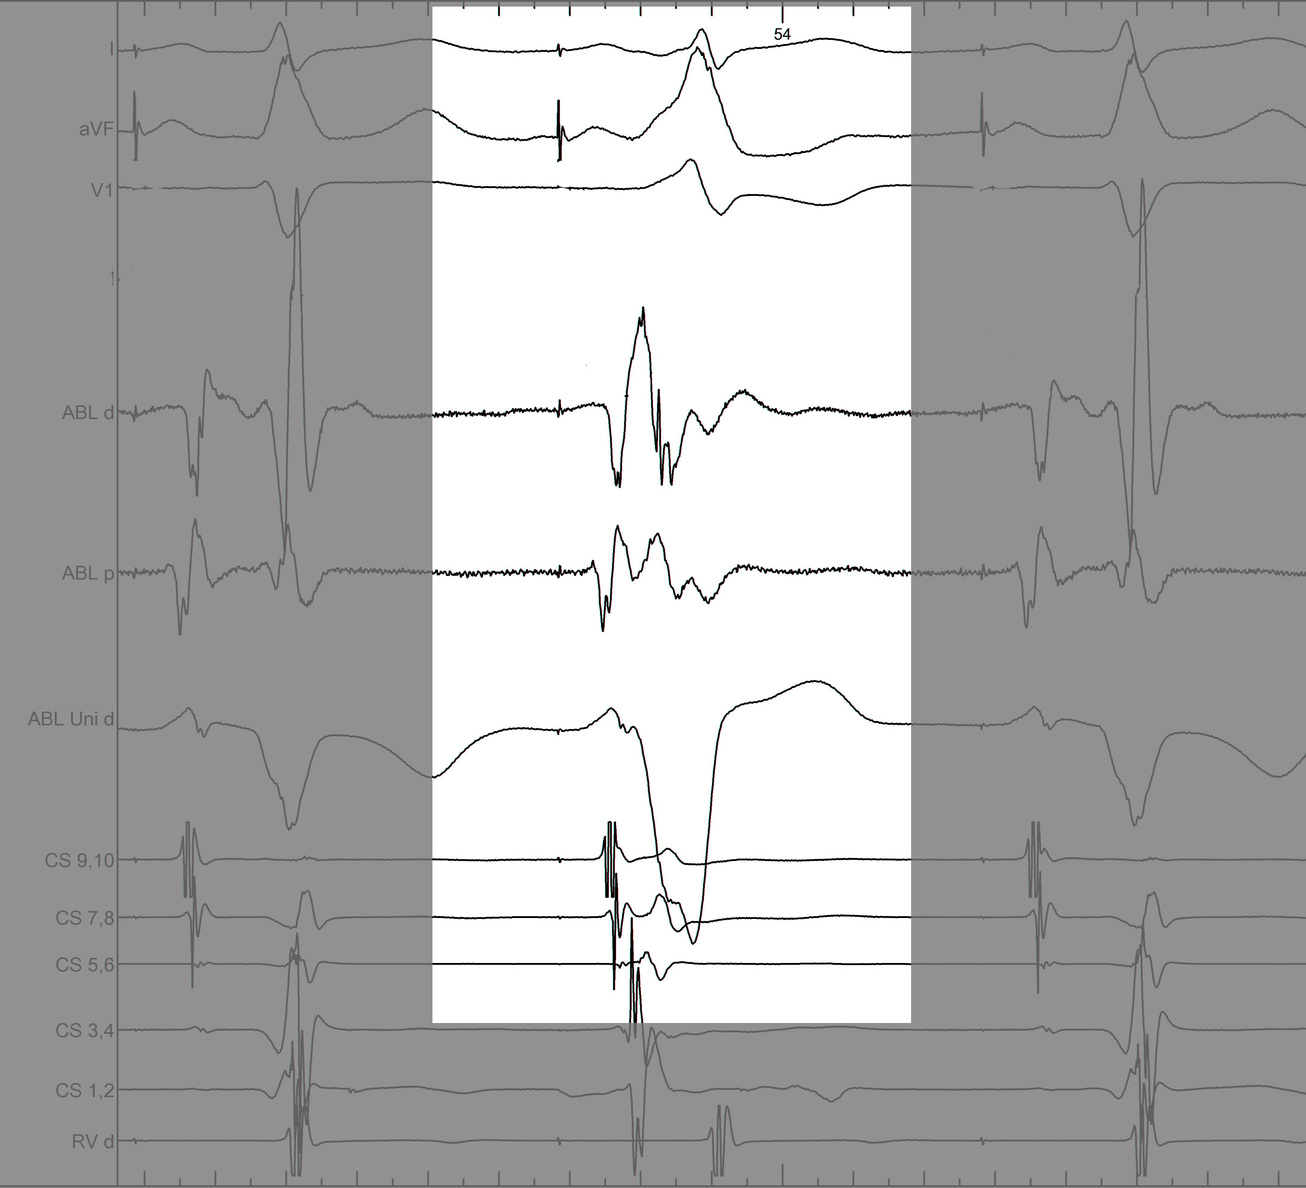

Use unipolar EGMs

uni.jpg